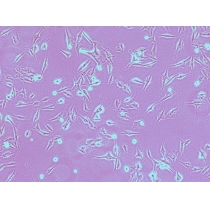

| 细胞名称 | HNE-2( HNE2)人鼻咽癌细胞 |

| 细胞形态 | 贴壁 |

| 细胞活力 | 95%(Viability by Trypan Blue Exclusion) |

| 培养条件 | RPMI-1640 +10% FBS;37℃,5% CO2 |

| 传代方法 | 建议1:2-1:3 两天换液一次 |